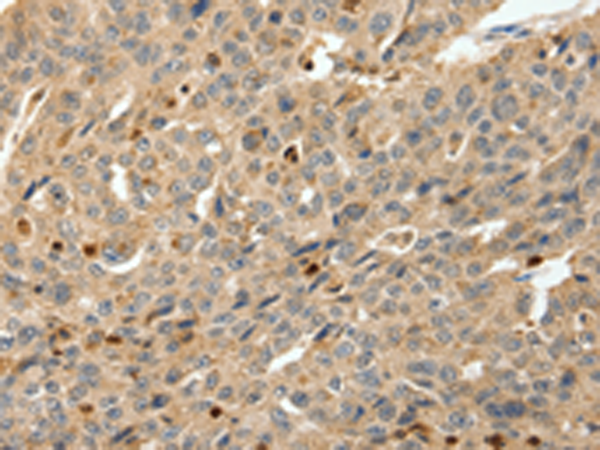

分类: 科研抗体货号: P04430别名: S9, Rpn6, p44.5应用: IHC反应种属: Human, Mouse, Rat